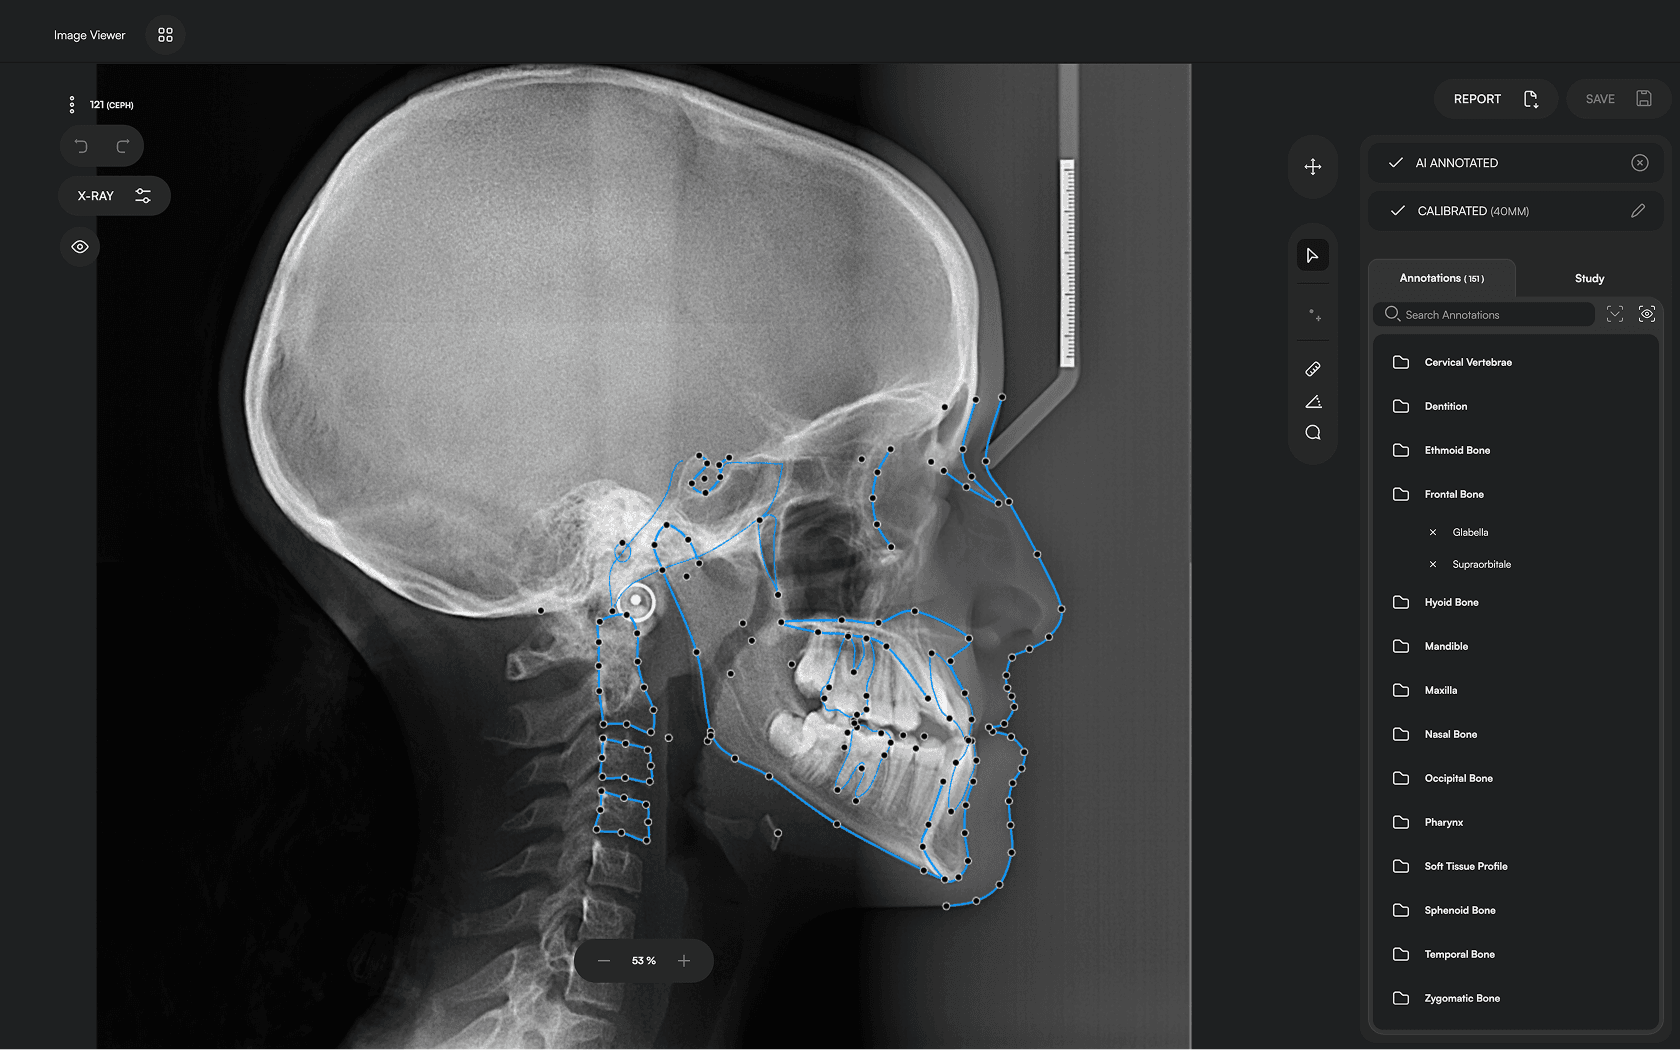

150+ landmarks traced in seconds

Diverse Analysis

Access automated studies like Steiner and Jefferson to assist in clinical assessment and enhance case evaluations.